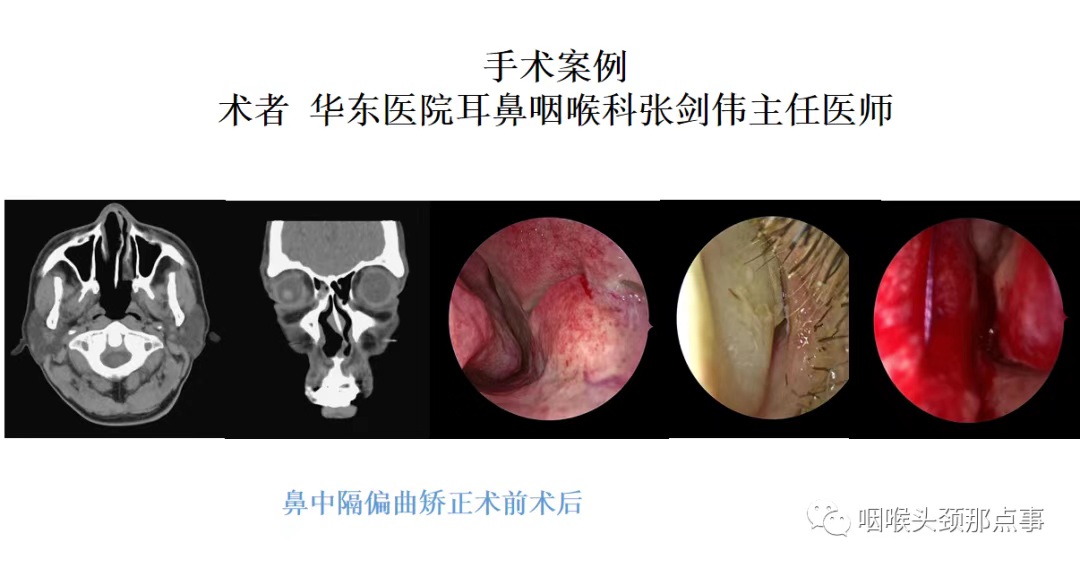

近十年一直被打呼、夜间憋气困扰的孙先生来到我的门诊,他和我说的最多的就是夜里鼻塞的厉害,翻身频繁,总感觉一侧睡时间长了就鼻腔堵得慌,最让他困扰的是鼾声特别大,老伴都不愿意和他在一个房间睡觉;还有近几年心脏也不舒服,检查发现有房颤,一直在吃抗凝药。给他做了初步检查发现他鼻中隔左偏特别明显,鼻甲也比较肥大,检查口咽发现他软腭稍有下垂,他今年68岁,肌肉松弛、张力下降也是一方面原因,其他平面没有特别狭窄;做了多导睡眠监测提示AHI指数18.6,最低血氧69%,他属于中度阻塞性睡眠呼吸暂停重度低通气综合征,应该与鼻腔平面阻塞关系较大;考虑患者一直服用抗凝剂,手术后出血风险较大,给他试用CPAP,也就是呼吸机,由于鼻腔平面阻塞,患者呼吸机耐受性很差,坚决要求手术治疗。经过综合评估,暂停长效抗凝剂,调整为短效抗凝治疗后患者做了鼻中隔偏曲矫正术及鼻腔扩容手术,为了安全起见,鼻中隔术后做了贯穿缝合,下鼻甲消融后也做了充分的止血,同时又做了鼻腔填塞。三天后患者鼻腔填塞物完全取出,当天晚上患者打呼就基本消失了,自己平时心脏不适也明显改善。出院后患者在我好大夫上给我留言和我说,现在夜间睡眠安静很多,恢复的很好,这是一个非常典型的鼻腔阻塞导致的阻塞性睡眠呼吸暂停综合征的患者。

首先就是如上面所讲的鼻中隔偏曲,鼻中隔偏曲在人群中很常见,这是由于人体结构在生长发育过程中不平衡有关,每个人多多少少鼻中隔都会有点偏曲,一般没有明显症状;但是如果偏曲明显,就会出现结构性鼻炎,也就是说鼻中隔向一侧偏曲时,由于偏曲侧空间狭窄,另一侧相对空间较大,但是人体为了保持平衡,空间较大侧鼻腔的鼻甲会出现代偿性肥大,从而导致患者双侧鼻腔均出现明显的阻塞,鼻甲有鼻甲周期,我们夜间经常翻身就是鼻甲周期发挥了重要作用,也就是说我们向哪个方向卧位,同方向的鼻甲会肿大,比如我们向右侧卧位,右侧鼻甲会变大,促使我们不自主的向左侧卧位,如此反复,促使我们夜间睡觉时翻身,避免夜间长期一个姿势睡觉。一般人这种鼻甲周期是没有感觉的,不会有鼻塞症状,但是对于有鼻炎的患者,他们就能明显感受到这个周期所带来的的困扰,会感觉鼻塞,这也就是为什么孙先生夜间会频繁翻身、鼻塞、憋气的原因。

鼻中隔偏曲